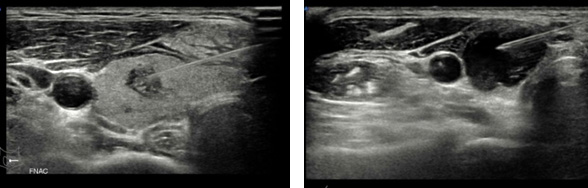

갑상선 세침 흡인검사

전 세계적으로 갑상선 결절의 악성 여부를 진단하는 방법입니다.

갑상선 세침 검사는 작은 주사기를 이용하여 갑상선 결절 안의 세포를 흡인한 뒤, 현미경을 통해 살펴보고 이 세포의 모양을 확인하는 검사로, 비교적 간단하고 통증과 합병증이 거의 없는 안전한 검사입니다.